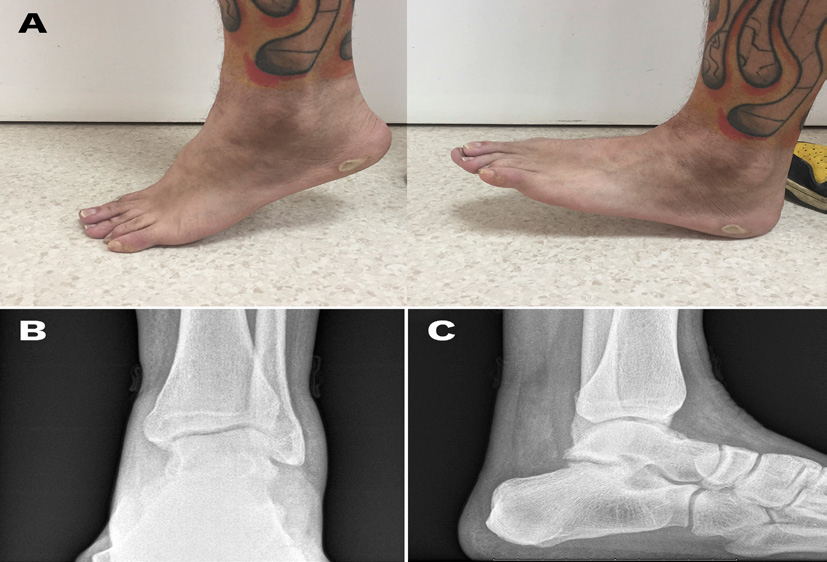

Closed reduction of the dislocation was carried out under sedation by traction with the knee flexed, followed by eversion of the foot with plantar flexion of the ankle and, finally, dorsal flexion of the ankle (Figure 2A). After the reduction, the presence of dorsalis pedis and posterior tibial pulses, capillary nail refill and distal sensitivity, as well as the correct oxygenation by digital pulse oximetry were clinically verified. The affected joint was immobilized with a below-the-knee splint. The correct reduction of the dislocation was confirmed by conventional X-ray in two projections (Figure 2B & 2C).

Figure 2A ankle appearance after close reduction; B: conventional X-Ray (B, anteroposterior view; C, lateral view) showing correct reduction of the dislocation.